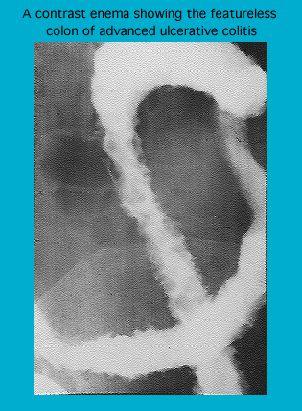

Contrast radiograph in advanced ulcerative colitis